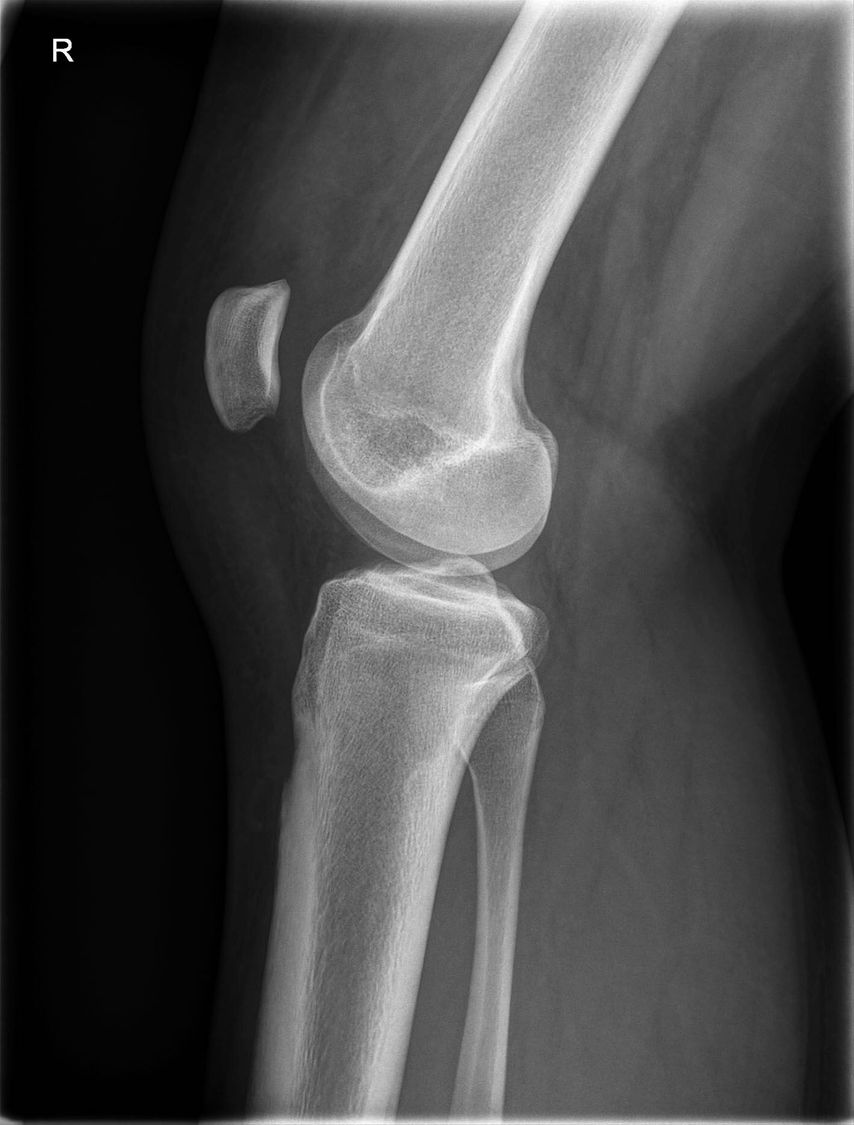

13-jährige Patientin, Zustand nach MPFL-Plastik

4 Jahre nach der Operation stürzte die Patientin neuerlich auf das Kniegelenk, was eine Reruptur der MPFL-Plastik zur Folge hatte (Abb. 1). Die Revisions-MPFL-Plastik erfolgte mit der Quadrizepssehne.